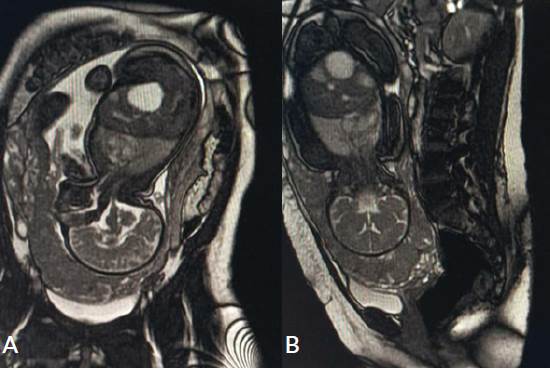

La resonancia magnética suministrada al momento del ingreso reportó: útero grávido, placenta en posición anteroinferior hasta el cérvix, vejiga urinaria parcialmente plenificada, sin evidencia de lesiones parietales e intraluminales, ampolla rectal centrada, de paredes delgadas, sin lesiones parietales ni intraluminales (Figura 4).

Figura 4 Resonancia magnética abdominopélvica realizada el día 12/05/2023. A: Corte sagital a nivel abdominal en T1, donde se evidencia útero grávido con feto en posición cefálica, sin anormalidades visibles en sus órganos internos. Placenta en posición anteroinferior hasta el cérvix. B: Corte coronal de abdomen donde se evidencia feto sin anormalidades visibles y en contacto con placenta